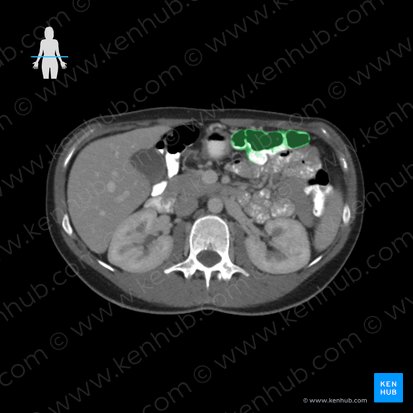

Colon transverso

El colon transverso es la segunda parte principal del colon. Se extiende entre las flexuras cólicas (esplénicas) derecha e izquierda, abarcando el hipocondrio derecho, epigastrio e hipocondrio izquierdo del abdomen. La curvatura mayor del estómago y el ligamento gastrocólico son superiores al colon transverso, mientras que el omento (epiplón) mayor cuelga y se extiende hacia abajo.

El colon transverso es intraperitoneal. Un mesenterio peritoneal (mesocolon transverso) lo une a la pared posterior de la bolsa omental (epiploica). Esto forma dos compartimentos abdominales llamados compartimentos supracólico e infracólico.